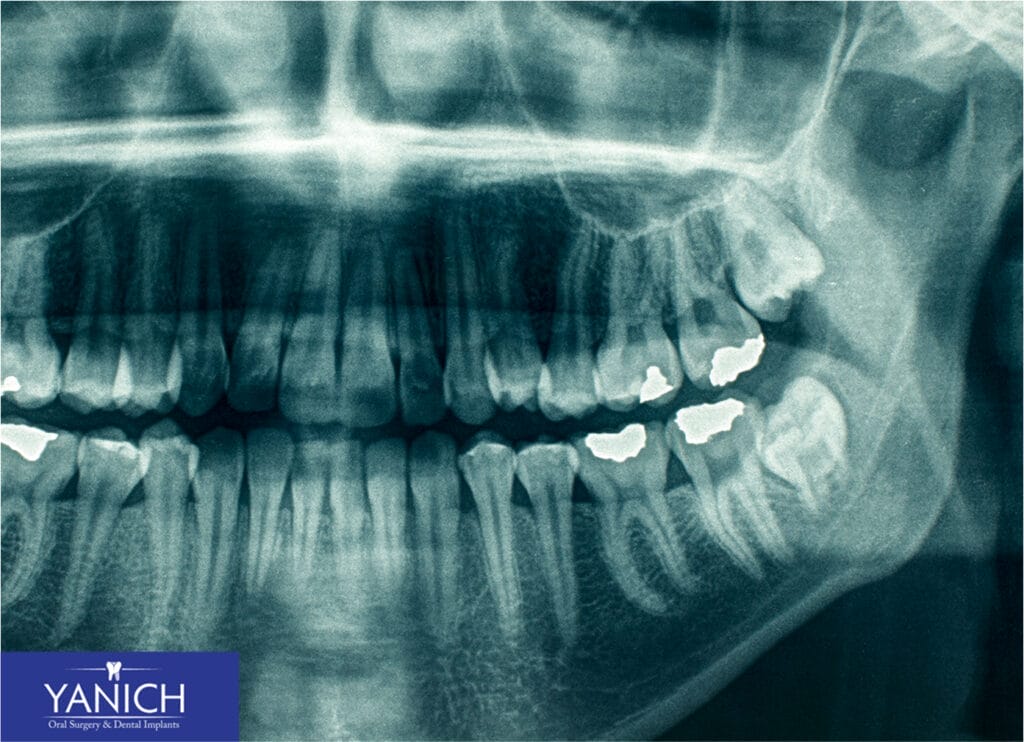

If you’re experiencing any of the warning signs we’ve discussed, it’s time to make an appointment with your dentist. During your visit, we’ll perform a thorough examination that typically includes a visual examination of your mouth, X-rays, or panoramic imaging to see the position of your wisdom teeth below the gum line, a discussion of any symptoms you’re experiencing, and a review of your dental and medical history.